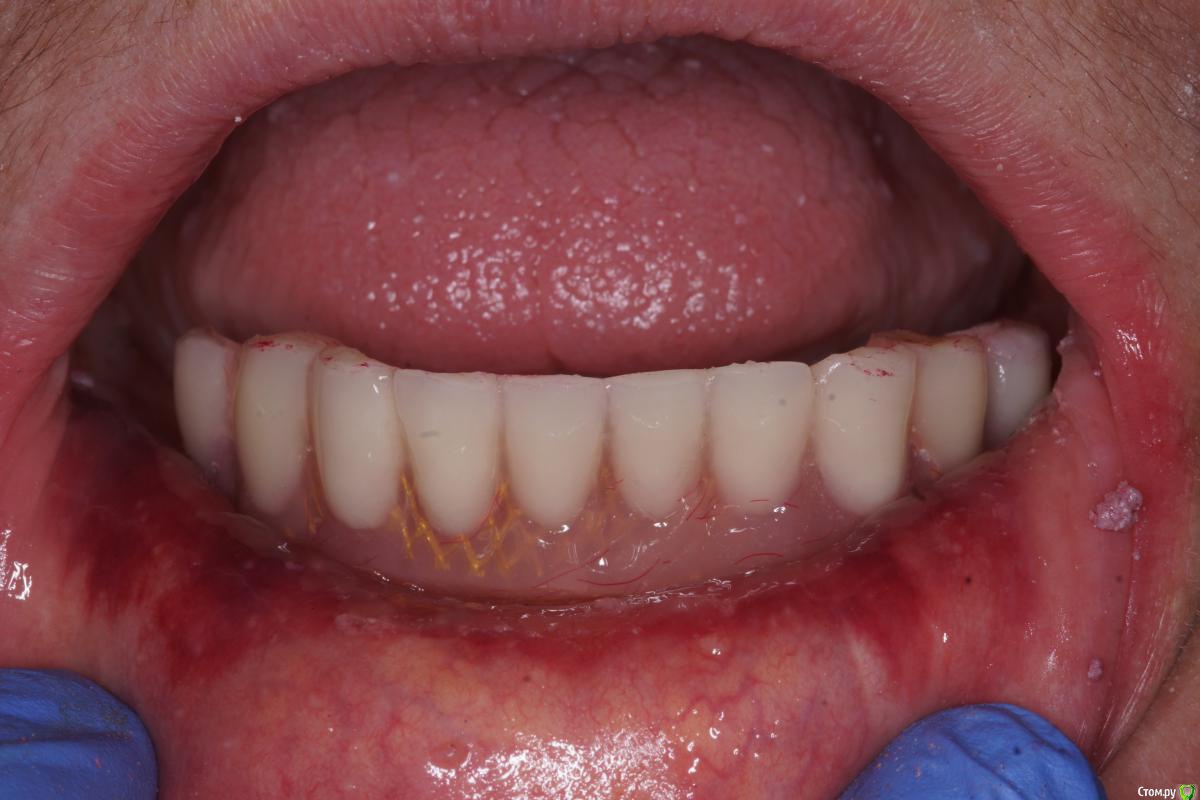

Во рту post-36568-0-13353100-1566455461_thumb.jpg post-36568-0-30978400-1566455479_thumb.jpg